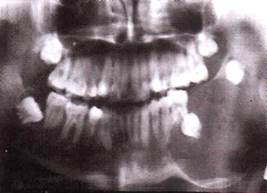

Рентгенологическая картина

Возможны следующие варианты амелобластомы:

1. Ряд округлых полостей.

2. Одна костная полость, окруженная множеством более мелких полостей.

3. Ряд округлых полостей, в 1-2 из которых заключен зубной фолликул или сфор­мированный зуб.

4. Многоугольные полости.

5. Крупнопетлистая структура кости за счет множества мелких кист.

6. Несколько единич­ных крупных кистозных полостей.

7. Одна большая кистозная полость с неровными края­ми.

8. Одна большая полость, в которую обра­щены корни зубов (напоминает радикулярную кисту).

9. Одна большая киста, в которую обра­щена коронковая часть непрорезавшегося зуба. Этот вариант напоминает фолликулярную кис­ту.

Важнейшей рентгенологической чертой адамантином является различная степень прозрачно­сти тени полостей особенно четко выраженной в поликистозных адамантино­мах. Центральные отделы кистозных полостей прозрачнее, чем краевые. В однока­мерных адамантиномах удается видеть полоску полутени вдоль костных границ опухоли. Нередко отмечается резорбция корней зубов в области опухоли.